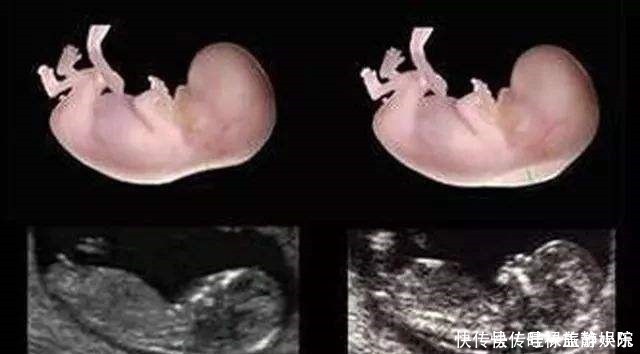

检查时间:怀孕中期,一般在孕24周时检查。现在不少医院大排畸检查,直接做四维B超,会看的更清楚些。排畸检查是孕期最系统的胎儿发育情况的检查,除了检查胎儿的外表可能存在的畸形外,也会检查胎儿内脏的发育情况等。

京妈建议:① 四维排畸检查,一般需要提前预约,因此孕妈要提前咨询医生或护士,提前预约检查的时间;② 四维排畸检查因为看的比较仔细,所以检查时间较长,孕妈要有心理准备,不必担心:检查这么长时间是不是胎儿有问题;③ 孕妈提前做好准备,耐心的配合医生检查,别着急;④ 如果在检查过程中,胎宝宝胎动很少,孕妈可以起来走动走动,或喝点水、吃些甜食来刺激胎宝宝活动;⑤ 如果没能一次检查成功,比如胎儿正好挡住了某些部分,看不清楚,那就可以听从医生建议,安排时间再次检查,但不必慌张;⑥ 避免问医生些不该问的问题,比如关于胎儿性别,我国禁止非医学需要的胎儿性别鉴定,所以孕妈要配合医生,尽量避免问,如果问了医生不回答也是正常的,不要因此对医生生气或作出出格行为。⑦ 在胎儿大排畸检查时,一般会做胎儿超声心动检查,主要是了解胎儿各个心脏瓣膜以及心室、心房的发育情况,排除先天性心脏病的可能,孕妈听从医生的安排和建议就好。